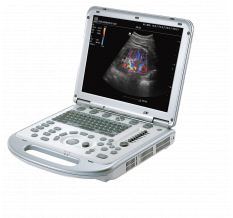

Точная визуализация и диагностика

Благодаря платформе AIT, ультразвуковая система Resona A20 формирует ультразвуковые изображения с исключительной четкостью, что особенно важно в сложных клинических случаях. Технология HD Scope+ основана на инновационном адаптивном формировании ультразвукового луча, что позволяет еще точнее выявлять мельчайшие детали патологий и значительно усиливает диагностические возможности ультразвука.

Технология HD Scope+

Программно-аппаратная технология Scope+ позволяет извлекать больше полезной информации из эхосигналов. В зависимости от конкретных клинических задач, метод обработки данных FreeIQ обеспечивает прицельное улучшение качества изображения в нужной области. Режим HD Scope+ в сочетании с B-режимом обеспечивает одновременное отображение двух изображений в реальном времени, что позволяет детально рассматривать патологические изменения в тканях.

-

Гепатоцеллюлярная карцинома (ГЦК)

-

Узел щитовидной железы

-

Новообразование молочной железы